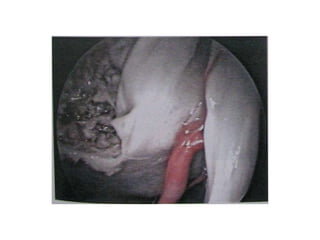

Retrosigmoid approach –

observe 9th nerve near

cochlear aqueduct [CA]